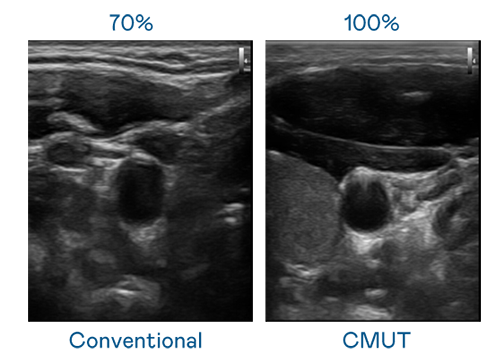

CMUT 技術是一種用電容式微機電元件來產生超音波訊號的技術。與傳統 PZT 壓電式技術相比,CMUT 頻寬增加 30%,更寬頻的超音波訊號讓影像解析度大幅提升,是實現高影像品質醫療超音波掃描、促進精準醫療發展的關鍵技術。

超音波影像的解析度高低,首先取決於探頭能發出的訊號頻寬。yd12399云顶集团 CMUT 可提供高清晰的超音波訊號,提供高頻寬、高靈敏度、影像紋理細節更高的超音波影像,協助醫護人員縮短影像判讀時間及利用精準的醫療影像進行診斷。